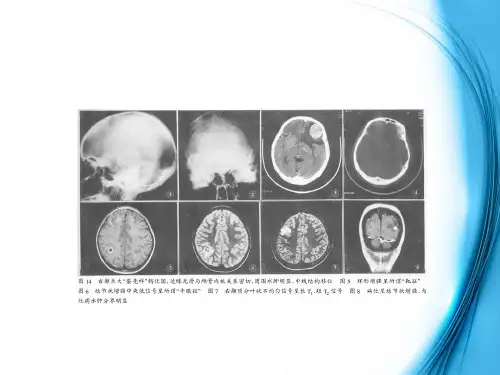

颅内感染性疾病的影像学诊断颅内感染性疾病的影像学诊断一、引言颅内感染性疾病是指发生在颅内的疾病,并由细菌、真菌或寄生虫等微生物引起。

影像学在颅内感染性疾病的诊断中起着重要的作用,本文将详细介绍颅内感染性疾病的影像学诊断方法及其表现。

二、脑膜炎⒈浸润型蛛网膜炎的影像学表现⒉化脓性脑膜炎的影像学表现⒊乳状分泌物性脑膜炎的影像学表现三、脑脓肿⒈化脓性脑脓肿的影像学表现⒉真菌性脑脓肿的影像学表现⒊寄生虫性脑脓肿的影像学表现四、脑脓肿周围脊膜炎⒈化脓性脑脓肿周围脊膜炎的影像学表现⒉真菌性脑脓肿周围脊膜炎的影像学表现⒊寄生虫性脑脓肿周围脊膜炎的影像学表现五、脑脓肿脑膜炎复合体⒈化脓性脑脓肿脑膜炎复合体的影像学表现⒉真菌性脑脓肿脑膜炎复合体的影像学表现⒊寄生虫性脑脓肿脑膜炎复合体的影像学表现六、脑室内感染⒈化脓性脑室内感染的影像学表现⒉结核性脑室内感染的影像学表现⒊隐球菌性脑室内感染的影像学表现七、颅骨髓炎⒈化脓性颅骨髓炎的影像学表现⒉结核性颅骨髓炎的影像学表现八、本文档涉及附件附件A: 颅内感染性疾病影像学案例图片九、本文所涉及的法律名词及注释⒈颅内感染性疾病:指发生在颅内的疾病,并由细菌、真菌或寄生虫等微生物引起。